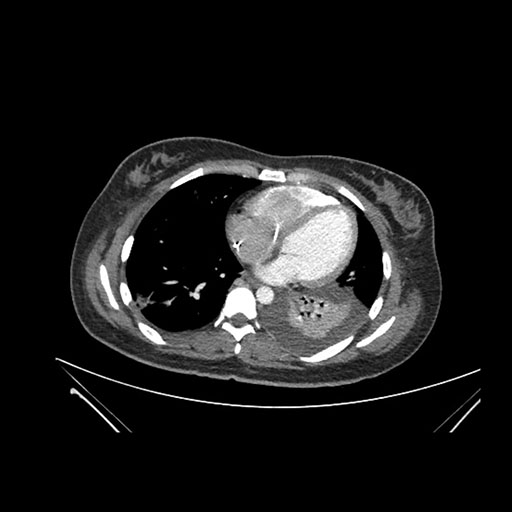

Axial Arterial

Axial Venous